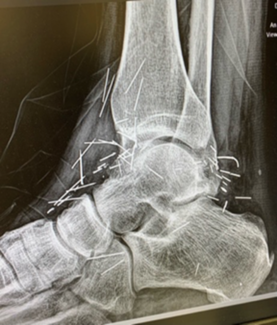

Total Talus Replacement

Jannani Krishnan, DPM; Bhavkaranjeet Kaur, DPM; James Brian Warne, DPM

Total talus replacement is emerging as a powerful salvage option for patients with advanced avascular necrosis (AVN), failed ankle arthroplasty, or end-stage ankle arthritis. This article explores the advantages of 3D-printed...